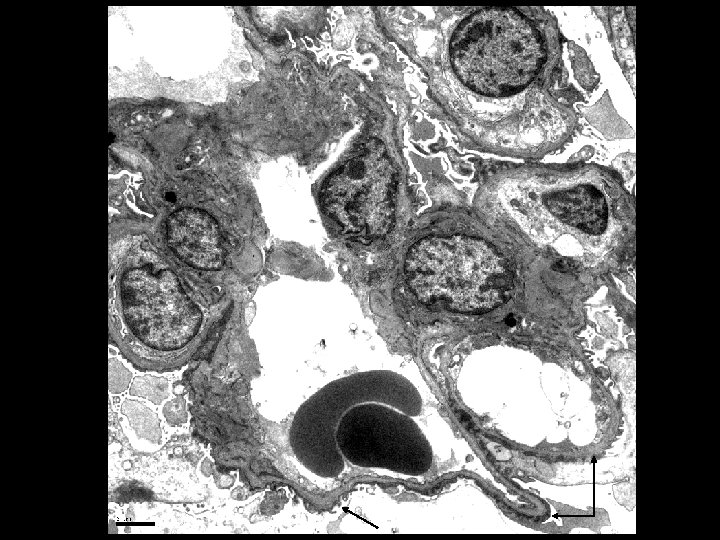

Electron Microscopy • Lamellation, thickening and thinning of GBMs

Alport’s Syndrome • Recurrent hematuria • Nerve deafness • Usually presents in early 20’s • Classic renal biopsy features by EM – Thickened and Thinned GBM – Lamination and Rarefaction – Grains